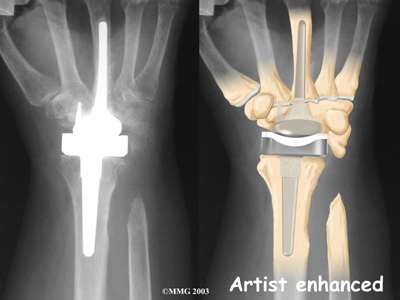

Modern artificial wrist joints are made of metal and plastic. The part that fits against the end of the radius bone of the forearm is called the radial component. It is made up of two pieces. A flat metal piece is placed on the front part of the radius. It has a stem that attaches down into the canal of the bone. A plastic cup fits onto the metal piece, forming a socket for the artificial wrist joint.

The part that replaces the small wrist bones is called the distal component. This piece is made completely of metal. It is globe shaped to fit into the plastic socket on the end of the radius. The metal distal component is attached by two metal stems that fit into the hollow bone marrow cavities of the carpal and metacarpal bones of the hand.

The plastic used in artificial joints is tough and slick. It allows the two pieces of the new joint to glide easily against each other as you move your wrist. The ball and socket allow movement of the wrist in all directions.